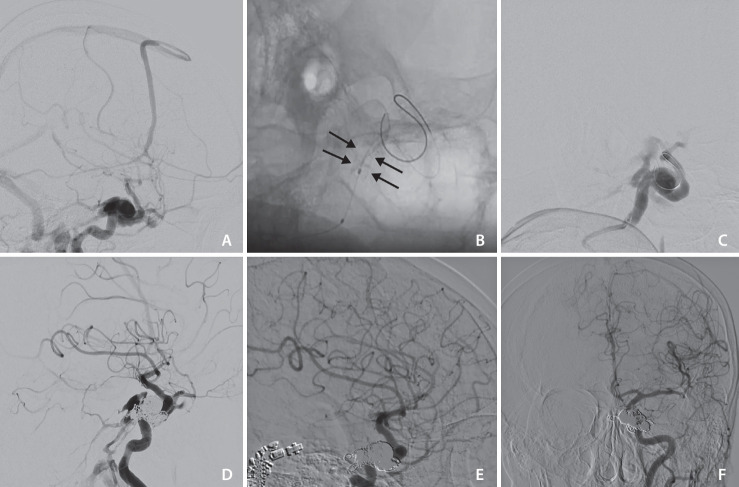

The widely accepted option for treating traumatic direct carotid-cavernous fistula (dCCF) has been endovascular treatment using detachable balloons, coils, or embolic agents. Covered stent deployment has been applied by a few operators and has shown promising results. This is a retrospective study on patients with dCCF treated by an endovascular approach using BeGraft, a covered stent. In 4 cases, this device was successfully deployed without any complications. Immediate complete occlusion was achieved in 3 patients (75%) after deployment of the covered stents. One patient required transvenous coiling for occlusion of the remaining endoleak. Follow-up imaging demonstrated 100% fistula occlusion with complete internal carotid artery patency. No early or late complications occurred following treatment. In conclusion, the BeGraft-covered stent could be a promising safe and effective alternative option for the endovascular treatment of dCCF.

治疗外伤性颈动脉-颈静脉直瘘(dCCF)的公认方法是使用可拆卸球囊、线圈或栓塞剂进行血管内治疗。有盖支架置入术已被少数操作者采用,并显示出良好的效果。这是一项回顾性研究,研究对象是使用有盖支架 BeGraft 进行血管内治疗的 dCCF 患者。在 4 个病例中,该装置被成功植入,未出现任何并发症。有 3 名患者(75%)在使用覆盖支架后立即实现了完全闭塞。一名患者需要经静脉卷曲以堵塞剩余的内漏。随访成像显示瘘管100%闭塞,颈内动脉完全通畅。治疗后未出现早期或晚期并发症。总之,BeGraft 包覆支架有望成为血管内治疗 dCCF 的一种安全有效的替代选择。